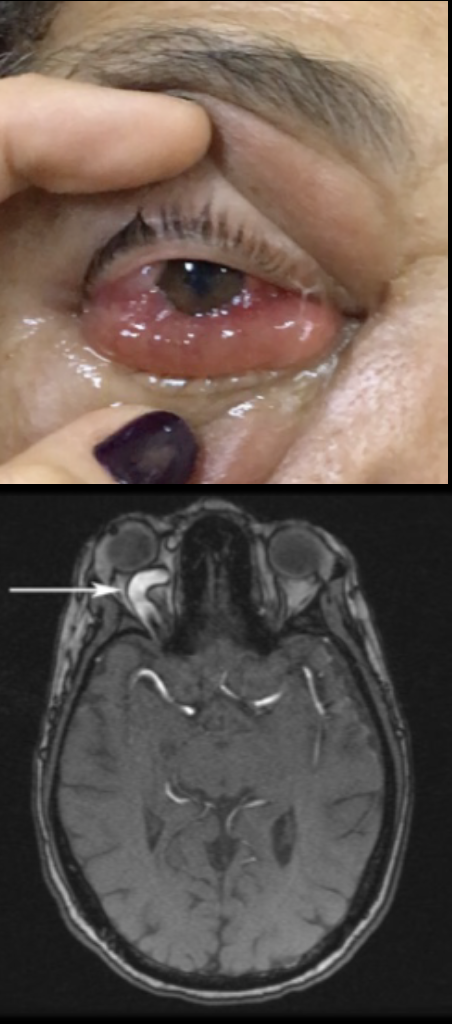

Qual a alteração clássica nos exames de imagem na fístula carótido-cavernosa?

Aumento do calibre da veia oftálmica superior

Quadro unilateral de aumento do calibre e tortuosidade dos vasos episclerais, aumento da PVE e aumento da PIO